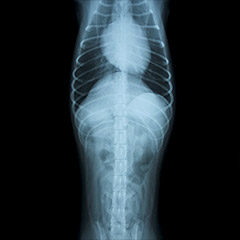

通常レントゲン検査、造影検査

ヒトと同じように、動物でもレントゲン検査は欠かせない検査です。

レントゲン検査は同時に複数の臓器の位置関係・大きさ・形の把握ができることが大きなメリットです。反面、臓器内部の詳細構造は診ることができません。特に整形外科分野で大きな力を発揮する他、胸部(肺野の診断や心臓の大きさの評価)でも重要視される検査です。腹部では複数の臓器が重なるため、胸部に比べて診断力は低下しますが、それでも、肝臓が腫れている、腫瘤や異物が認められ、それがどこにどのような大きさであるか、尿管・膀胱結石の有無…etc.有用性は限りなくあります。